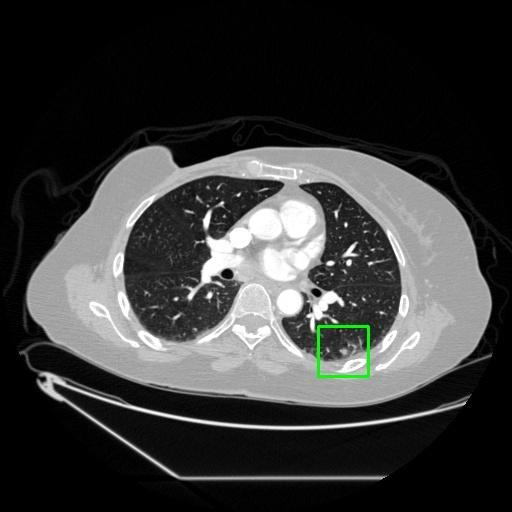

We developed an AI-based system using deep learning models for analyzing lung CT scans to detect and classify pulmonary nodules. We chose the YOLOv11 architecture for its enhanced object detection capability and adapted it specifically for medical imaging, incorporating pixel-level precision and severity classification.

Classification into three severity levels with colored bounding boxes.

Successfully built and deployed an AI model (YOLOv11) capable of detecting lung nodules in CT scans with high accuracy and real-time performance.

Designed a severity classification system that categorizes nodules into null, moderate, and severe using colored bounding boxes, assisting in rapid clinical decision-making.